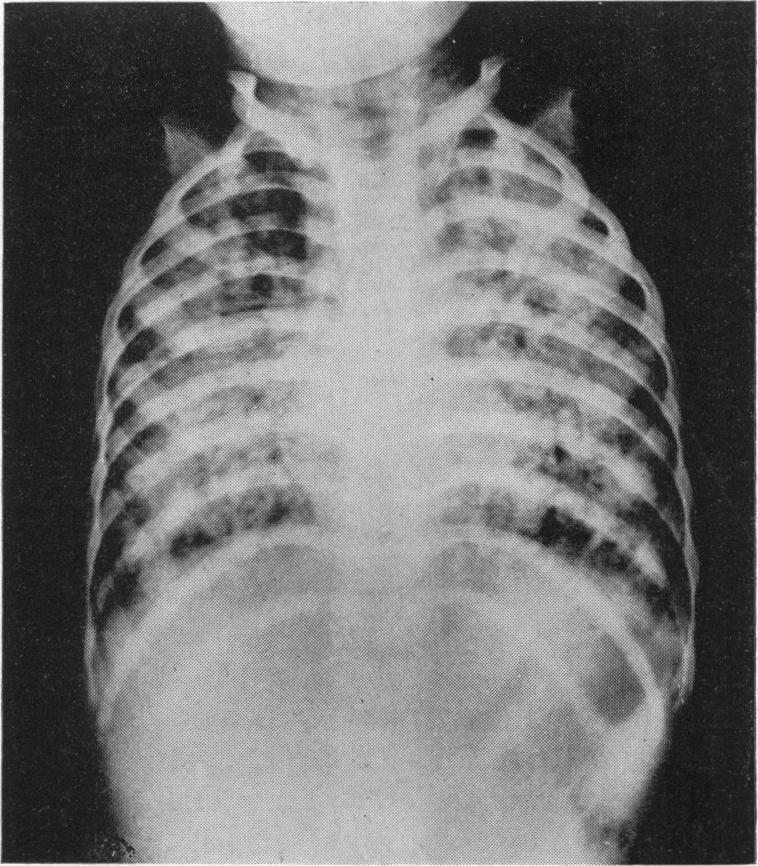

Arch Dis Child. 1961 Oct;36(189):530-6. doi: 10.1136/adc.36.189.530.